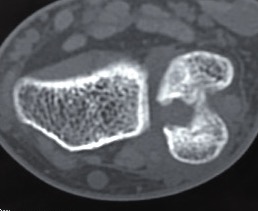

DRUJ instability

Post traumatic distal ulna osteoarthritis